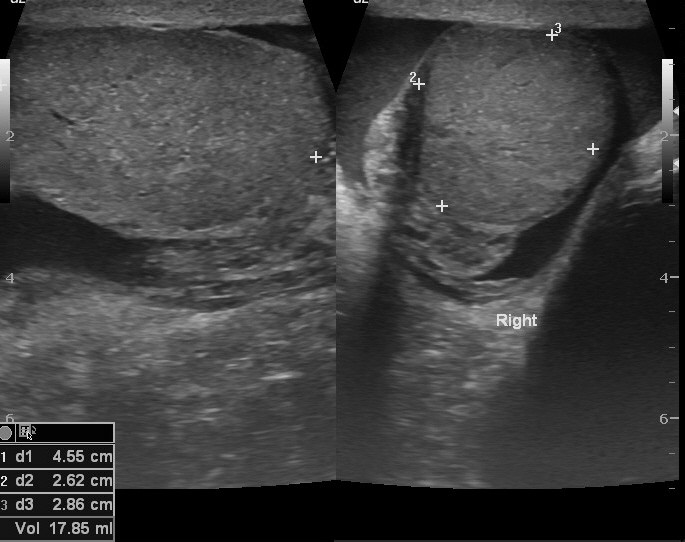

USG jąder w Lublinie w Centrum Medycznym PROVIVO to bezpieczne i nieinwazyjne badanie obrazowe, które pozwala ocenić zawartość worka mosznowego, w tym jądra, najądrza, ich osłonki oraz obecność żylaków powrózka nasiennego.

Badanie umożliwia ocenę jąder, najądrzy, osłonek jąder oraz struktur znajdujących się w obrębie worka mosznowego. Pozwala także wykryć obecność żylaków powrózka nasiennego, które mogą mieć znaczenie kliniczne i wpływać na dalsze postępowanie diagnostyczne lub lecznicze.

USG jąder jest jednym z podstawowych badań obrazowych wykorzystywanych w diagnostyce zmian w obrębie moszny. Dzięki niemu lekarz może lepiej ocenić przyczynę dolegliwości i zdecydować o dalszych krokach.